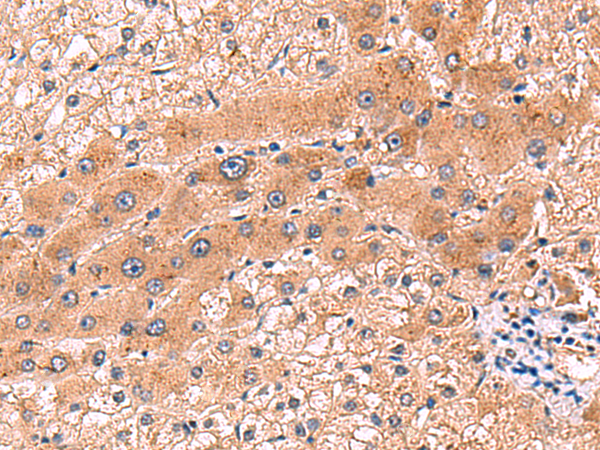

IHC positive control: |

Human liver cancer |

IHC Recommend dilution: |

80-400 |